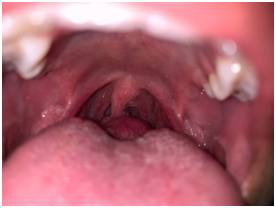

We present a case of a 18 years old male who presented to our outpatient clinic with chief complaints of persistent cough and foreign body sensation since one month. He was completely asymptomatic before that. There was no history of weight loss, prolonged fever, sputum production and sore throat. There was no history suggestive of hypothyroidism. On examination, there was a small soft cystic midline swelling of size 4x3 cm at the base of tongue extending to left lateral side (Figure 1). It was not bleeding on touch. Neck examination revealed absence of thyroid gland on palpation. There were no palpable neck nodes. Indirect laryngoscopy showed bilateral vocal cord mobility with normal endolarynx. Ultrasound neck showed absence of thyroid gland in normal anatomical location. Thyroid function test revealed T3- 1.31 ng/ml, T4-8.7ug/dl, TSH-24.18uiu/ml. After getting endocrinology opinion, patient was started on 50 microgram of L-thyroxine. Further evaluation in the form of contrast enhanced computed tomography scan neck revealed cystic swelling of 3x2 cm size with peripheral rim of enhancement suggestive of thyroid tissue at the base of tongue and absence of thyroid gland in normal anatomical location (Figure 2). Technetium 99m scan suggested increased isotope uptake at base of tongue and no uptake at the normal thyroid location.

Figure 1 Oropharyngeal examination showing lingual thyroid.